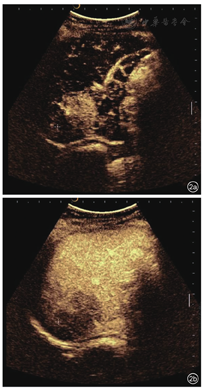

患者,女性,45岁,因糖尿病行体检无意间发现肝右叶肿物3 d入院。无腹痛、腹胀,无寒战、发热,无皮肤、巩膜黄染,无乏力,无体重减轻等。既往2型糖尿病病史,注射胰岛素治疗,血糖控制良好。无肝炎病史,无牧区居住史,无饮酒史,无肿瘤家族史。查体:体温36℃,肝、脾肋下未触及,腹平软,移动性浊音阴性。实验室检查:白细胞计数10.29×109/L,肝功能正常,乙型肝炎表面抗原和核心抗原阴性,甲胎蛋白(alpha fetoprotein,AFP)、糖类抗原19-9(carbohydrate antigen 19-9,CA19-9)及癌胚抗原(carcino-embryonic antigen,CEA)均阴性。腹部超声示:肝脏回声均匀,肝右叶被膜下探及低回声,约5.9 cm×3.6 cm,形态不规则,边界不清,周围无声晕,后方回声未见增强,内未见明显血流信号(图1)。超声诊断:肝右叶肿物,声像图不支持典型肝癌,血管源性病变待排。静脉团注2.4 ml声诺维造影剂,肝脏超声造影示:肝右叶上段可见一大小为5.3 cm×3.4 cm的弱回声团,形态不规则,超声造影呈动脉期高增强,门脉期及延迟期低增强,呈"快进快出"模式(图2)。超声造影诊断:肝右叶实性占位,倾向恶性,建议超声引导下穿刺活检明确性质。腹部CT示:肝右后叶肿物,边界不清,大小约4.1 cm×4.8 cm,分叶状,肿物密度欠均匀,平扫为低密度,增强扫描呈轻度延迟强化,病变侵犯门脉右支分支,致管腔狭窄,管壁水肿(图3),倾向炎性肉芽肿性病变,与肿瘤待鉴别,建议穿刺活检。腹部MRI示:肝右后叶肿物,范围约3.6 cm×4.8 cm,分叶状,边界不清楚,T1加权像(T1 weighted image,T1WI)低信号,T2加权压脂像(T2 weighted image/fat suppression,T2WI/FS)稍高信号影,弥散加权成像(diffusion weighted image,DWI)高信号,增强扫描轻中度延迟强化,病变侵犯门脉右支分支(图4)。腹部MRI诊断:肝右后叶肿物,考虑肝癌可能性大。临床初步诊断:肝右叶实性占位,肝癌待排。患者行超声引导下肝肿物穿刺,组织病理学回报:可见梭形细胞增生,伴炎细胞浸润,结合免疫组化,考虑炎性肌纤维母细胞性病变(图5)。免疫组化结果显示:AE1/AE3(-),Vimentin(3+),Actin(1+),SMA(2+),Desmin(-),s-100(-),CD1a(-),CD21(-),CD35(-),CD68(3+),Ki-67(10%)。患者定期复查,未行治疗。5个月后复查腹部MRI示:原肝右后叶肿物,现已显示不明确,仅局部可见小片状异常信号,T1WI低信号,T2WI/FS低信号,DWI无明显扩散受限,增强扫描强化程度低于周围肝实质(图6),符合良性病变,请结合临床及病理。结合既往穿刺活检及影像学随访病灶消退病史,患者最终诊断为肝脏炎性肌纤维母细胞瘤。随访至今21个月,患者一般情况良好,无复发。

HIMT的超声、超声造影及CT、MRI影像表现多样,可能与不同病灶中病理组织学成分的比例及分布的差异相关[8]。超声常表现为单发、低回声肿块,内回声不均,形态多不规则,在特定切面可呈葫芦状、花生状或多结节融合状等特征性形态,部分病灶周围呈宽带状高回声[9],常无晕环,病灶后方多无明显增强或衰减。由于HIMT中纤维组织增生与慢性炎细胞比例不同,病灶凝固性坏死成分存在差异,随着病程的变化,其声像图表现多样。莫国强等[9]随访7例HIMT病灶发现,3例原低回声病灶内出现高回声,2例原病灶周边低回声晕消失并在11个月后为高回声圈替代,考虑为病变后期或陈旧性病灶内纤维组织增生、形成假包膜所致。本例患者肝脏肿瘤形态不规则,边界不清,与既往报道一致,结合穿刺病理,考虑肿瘤为病变后期,以增生为主。彩色多普勒血流显像(color Doppler flow imaging,CDFI)示肿块内多无明显血流信号,少数内部及周围可探及血流,血流阻力指数(resistance index,RI)多小于0.5[7]。由于不同病灶内新生血管血供程度不同,病灶内纤维化及炎性细胞成分有差异,HIMT超声造影模式亦可呈多样性,但文献报道[10,11],多数HIMT超声造影表现为恶性肿瘤增强模式,即"快进快出",因而超声造影有此模式者并不能完全排除HIMT可能。本例患者肝脏超声造影即因呈现"快进快出"灌注模式而被误诊为恶性。HIMT的CT影像学大多表现为肝内低密度肿块,其强化方式多样,有全瘤填充型、边缘强化型、分隔强化型、无强化型[12]。其特征性改变为动脉期病灶无强化或强化不明显,静脉期及延迟期不同程度、不同方式强化,即呈"慢进慢出"表现,以周边环状强化最多见[13]。本例患者CT表现为边缘延迟强化型,与既往研究相符。MRI平扫病灶多为圆形或类圆形,T1WI常呈低信号,T2WI呈中高信号,推测与病变处于进展期,以慢性炎细胞浸润为主,组织含水量较高有关,MRI与CT强化方式及程度相似,多表现为周边延迟强化[12]。有学者认为,此影像学表现体现了HIMT病理学特点,即病变以门静脉供血为主,肝动脉供血较少[14],病灶门脉期及延迟扫描边缘明显强化,考虑为造影剂从血管内渗透到血管外间隙后,聚集到纤维组织内,从而难以立刻廓清、导致延迟所致[15],病灶中心无强化反映了肿瘤内部细胞可能发生凝固性坏死。本例患者MRI表现T1WI低信号,T2WI稍高信号及周边延迟强化模式,与既往研究一致。HIMT超声造影模式与CT和(或)MRI增强模式不一致,分析可能与造影剂增强原理、从血管渗透途径不同有关。而HIMT在CT和(或)MRI影像学上另一个具有特征性的表现是清晰的门静脉分支可从肿瘤中穿过或包绕,表现为"挂果"征,同时常伴门静脉分支管壁增厚、管腔狭窄,后者为HIMT合并闭塞性静脉炎使门静脉分支受累所致[16]。本例患者CT和MRI均发现病变与门脉右支分支关系密切,MRI误诊为肝癌侵犯门脉右支分支,实则为门静脉右支穿入肿瘤,形成"挂果"征象,门静脉右支管壁水肿、管腔狭窄,实际上形成门静脉炎。HIMT的临床及影像学表现与少血供的肝细胞癌、胆管细胞癌、肝转移癌及肝脓肿有重合,除注意其影像学的特征表现外,还需结合其他因素综合考虑加以鉴别,如全身症状、肝炎和(或)肝硬化背景、肿瘤标记物(AFP、CEA、CA19-9)、既往肿瘤病史等,必要时可行超声引导下肝脏穿刺活检及免疫组化。